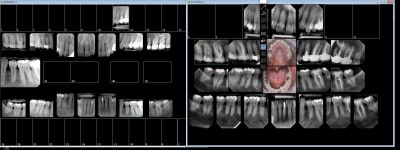

Tu peux faire ça aussi.

--

Dentiste qui en a plein le cul.